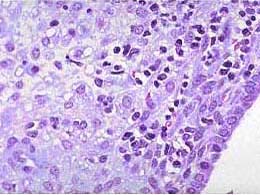

患者女性,39岁,因经量增多,淋漓不尽行诊刮术。送检内膜组织镜下见子宫内膜间质中大量浆细胞浸润,应诊断为 ( )

• D.慢性子宫内膜炎